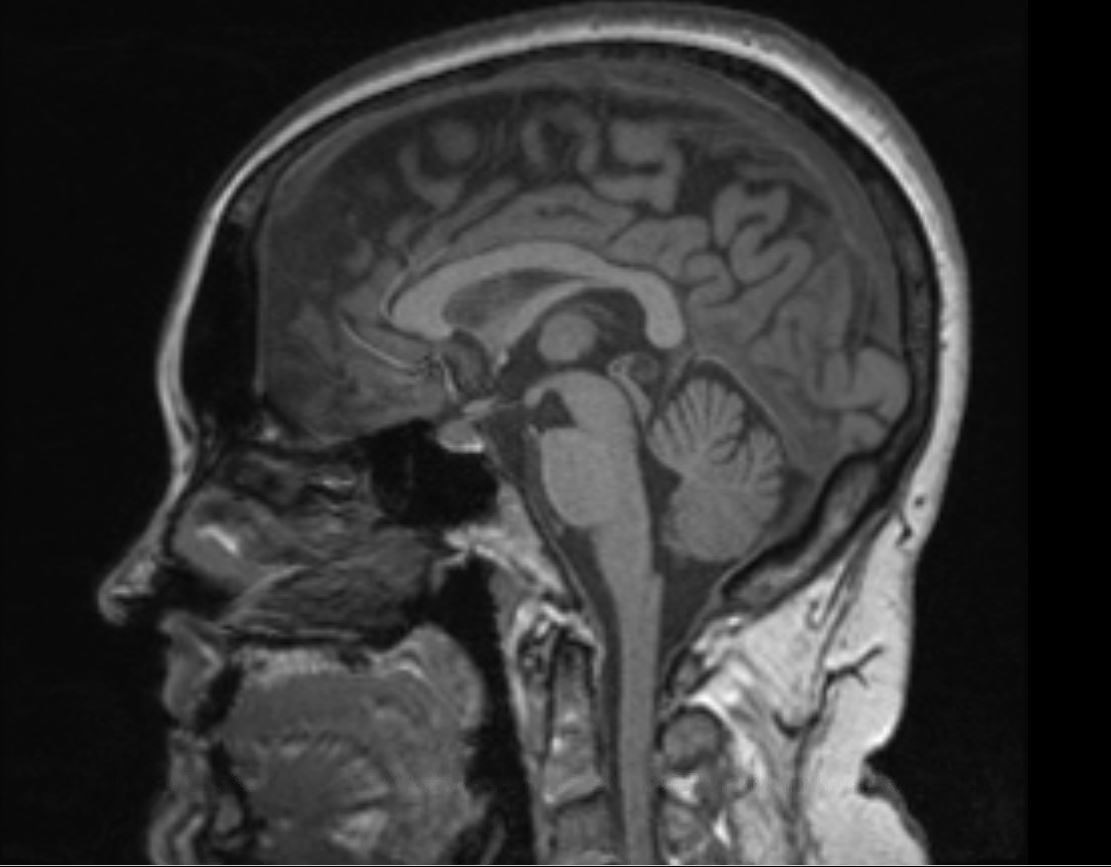

Poster image: A brain scan of a participant in one of Roberts' previous studies. Image courtesy of Donna Roberts.

Astronauts who spent a long period in microgravity demonstrated three major changes. The brain would shift upwards inside of the skull and, as the brain shifted upwards, the space for cerebrospinal fluid got narrowed. As did the central sulcus, a very important part of the brain that’s responsible for motor control.

Interestingly, other people have looked at this data before, but I think the brain-shift was missed as the first step in processing brain MRI scans, typically, is to strip the skull and just look at the brain. Any movement of the brain relative to the skull gets lost. And I think that’s unique about our study—we didn’t do that.